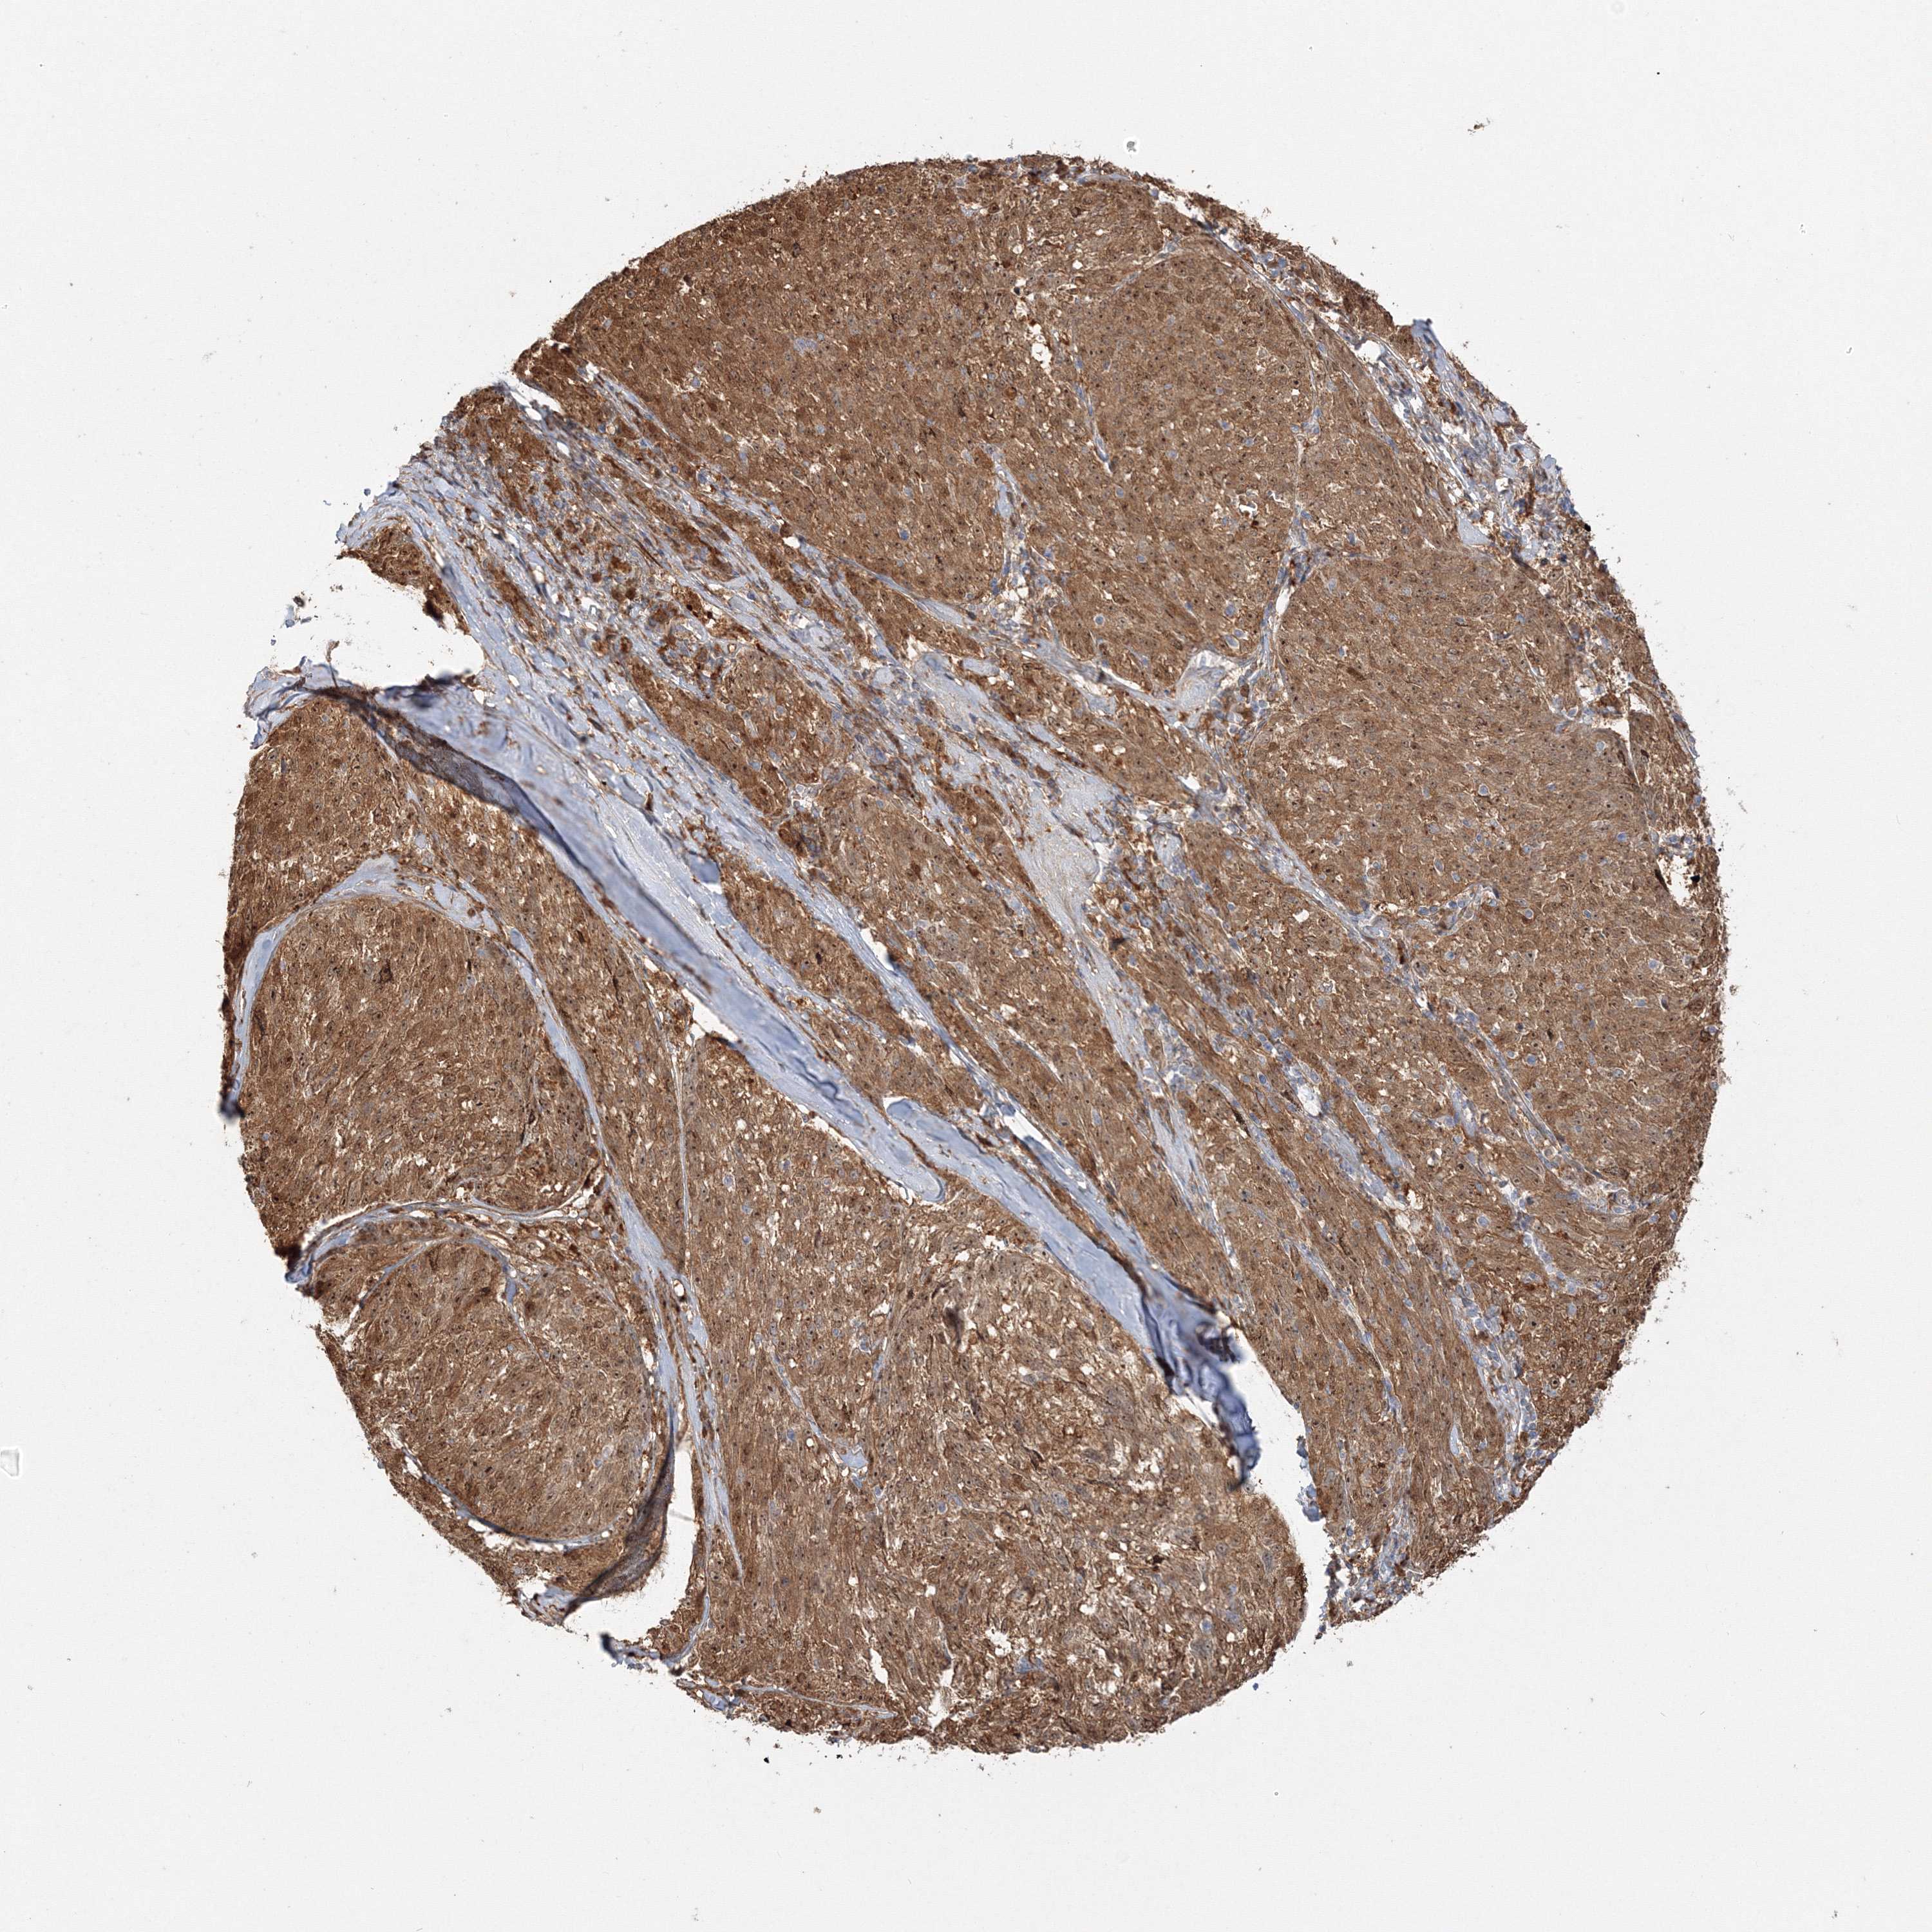

MELANOMA - Protein expressioni

A mouse-over function shows sample information and annotation data. Click on an image to view it in a full screen mode. Samples can be filtered based on level of antibody staining by selecting one or several of the following categories: high, medium, low and not detected. The assay and annotation is described here.

Note that samples used for immunohistochemistry by the Human Protein Atlas do not correspond to samples in the TCGA dataset.

Antibody stainingi

Antibody staining in the annotated cell types in the current human tissue is reported as not detected, low, medium, or high, based on conventional immunohistochemistry profiling in selected tissues. This score is based on the combination of the staining intensity and fraction of stained cells.

Each image is clickable and will lead to virtual microscopy that enables deeper exploration of all samples and also displays staining intensity scores, fraction scores and subcellular localization as well as patient and tissue information for each sample.

Antibody HPA036295

Antibody HPA036296

Staining

High

Medium

Low

Not detected

Intensity

Strong

Moderate

Weak

Negative

Quantity

>75%

75%-25%

<25%

None

Location

Nuclear

Cytoplasmic/membranous

Cytoplasmic/membranous,nuclear

Malignant melanoma, NOS

Malignant melanoma, Metastatic site